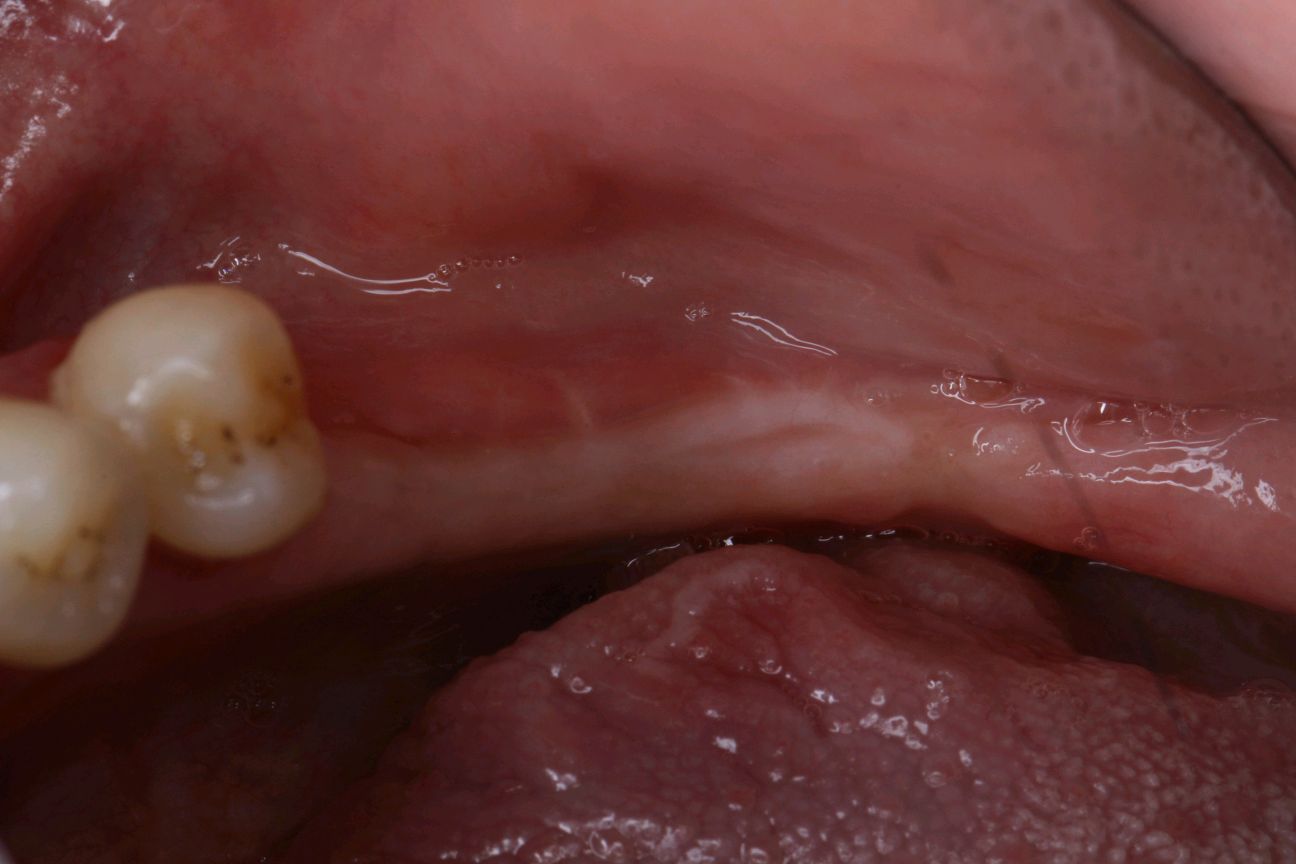

患者女30岁,左下后牙缺失已植入种植体,牙槽嵴呈刀刃壮,附着龈明显不足。角化牙龈缺乏易造成种植体抗炎屏障变弱,容易导致软组织炎症和边缘骨水平吸收。建议患者做游离牙龈移植术。通过获取自体健康游离龈瓣,移植到角化不足的患区,使种植体周围角化组织宽度增加,前庭沟加深。成功的话,会有良好的预后效果。